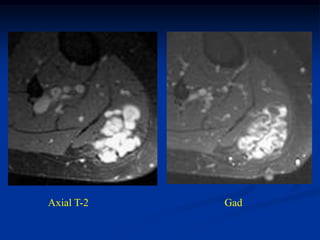

Case #297.2     Hemangioma forearm

46 yr male with

tender soft mass

forearm for years

Cor T-1   T-2   Gad

Sag T-1   T-2   Gad

Axial T-1         T-2

Gad

Case #297.2 Hemangioma forearm 46 yr male with tender soft mass forearm for years

• 310.

• 311.

• 312.

Axial T-1 T-2 Gad

• 313.